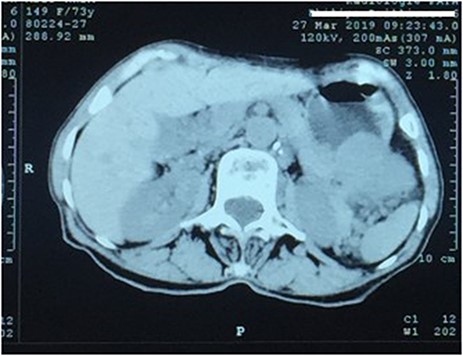

A 73-year-old woman was referred to our general surgery service. Her complain was intermittent gastric discomfort. There was no significant past medical history. There was no history of upper gastrointestinal bleed, or past surgical interventions with no abnormalities found on physical exam. An esophagogastroduodenoscopy (EGD) revealed a submucosal mass in the gastric body. Biopsy of the mass showed no evidence of malignancy. Computerized tomography (CT) scan of the abdomen showed an exophytic solid homogeneous mass along the greater curvature of the stomach and partly projected into the gastric lumen, causing smooth indentation measuring 8 × 8 × 6 cm3 (Fig. 1). The patient’s laboratory results were unremarkable. A presumptive diagnosis of GIST was made. The patient underwent successful wedge resection of the mass through laparotomy and the specimen was sent to pathology. On gross examination, a white intramural, nodular, solid mass measuring 8.7 × 8.8 × 6.7 cm was seen. A cut section revealed whirling trabeculation with a biphasic proliferation of compact hypercellular areas and myxoid hypocellular areas (Fig. 2). Sections from the tumor showed interlacing bundles of spindle cells, which had elongated nuclei, ill-defined cytoplasmic borders and palisading nuclei (Fig. 3). No nuclear atypia was noted. No mitotic activity and no necrosis were identified. There was no lymph node involvement and the surgical margin was negative for tumor cells. A histological diagnosis of a benign mesenchymal tumor was made. Immunohistochemistry (IHC) staining was strongly positive for S-100 (Fig. 4), whereas c-Kit, CD 34; DOG 1; smooth muscle actin (SMA), desmin and AE 1/AE 3 were negative. Hence, a final diagnosis of schwannoma was made. The postoperative period was uneventful and the patient was dismissed from the hospital after 5 days.

CT scan showing an exophytic mass in the great curvature of stomach wall